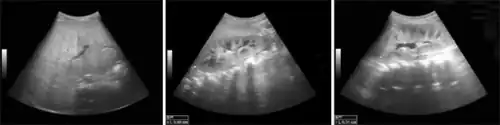

Hepatomegaly and nephromegaly was observed on ultrasonographic exam performed at approximately 2 years of age.